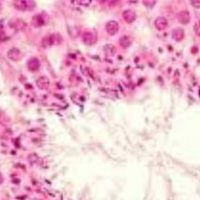

Esto es porque en su caso los problemas de piel son verdaderamente graves, con muestras de un envejecimiento acusado y una piel enferma por los efectos de las infecciones e inflamaciones que hayan podido surgir a lo largo de la vida. Una técnica para cada tipo de paciente.